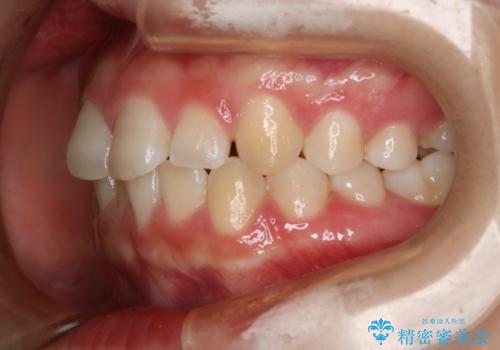

前歯のガタつきを治したい インビザライン・ライトパッケージ

- 前歯のガタつきの改善を主訴に来院された患者様です。

ガタつきによる上顎正中の空隙や歯の突出感も気にされていました。

費用を抑えたいとの事だったので歯の移動量なども考慮し、インビザライン・ライトパッケージでの治療を計画しました。

インビザライン・ライトパッケージでは歯の移動量が限られている分、費用と期間を抑えて治療することが出来ます。